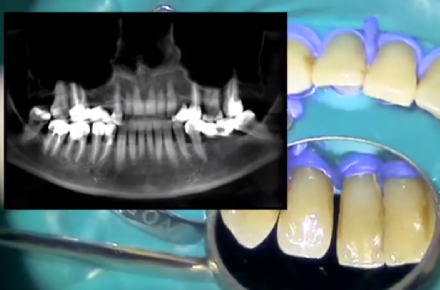

Как могут помочь ленты Ribbond при последствиях пародонтита